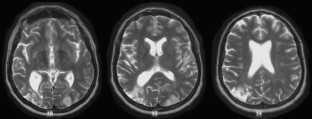

Extinction limited to visual motion perception in the left hemifield was demonstrated. The visual defect was attributed to a lesion involving the right occipito-temporo-parietal region in the presence of a left posterior infarction.

Fig 3